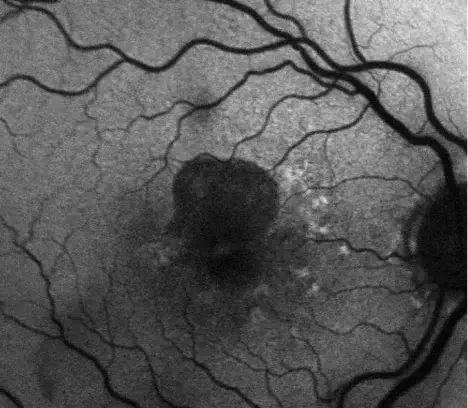

INDICATION

IZERVAY™ (avacincaptad pegol intravitreal solution) is indicated for the treatment of geographic atrophy (GA) secondary to age-related macular degeneration (AMD)